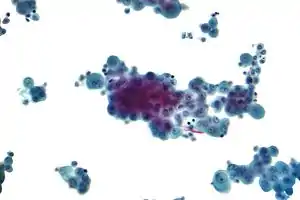

When a pleural effusion has been determined to be exudative, additional evaluation is needed to determine its cause, and amylase, glucose, pH and cell counts should be measured.

- If cancer is suspected, the pleural fluid is sent for cytology. If cytology is negative, and cancer is still suspected, either a thoracoscopy, or needle biopsy[5] of the pleura may be performed.

The most common causes of exudative pleural effusions are bacterial pneumonia, cancer (with lung cancer, breast cancer, and lymphoma causing approximately 75% of all malignant pleural effusions), viral infection, and pulmonary embolism.

- Cytopathology to identify cancer cells, but may also identify some infective organisms